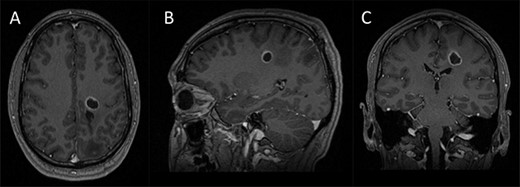

Integrated preoperative anatomical and functional brain mapping; (A–C) axial, sagittal and coronal fusion of T1-weighted MRI images with gadolinium and first eigenvector fractional anisotropy (FEFA); (D) whole brain tractography performed with StarTrack and visualized in TracViz according to deterministic spherical deconvolution algorithm. (E–G) fusion of CST with the ADC map; (H and I) nTMS mapping of the upper and lower limbs with hotspots for both upper and lower limbs identified with a marker (orange); (J and K) 3D Modelling of the tumour and the cortical and subcortical mapping of the CST with Stealth S8; (L) table summarizing the nTMS variables (resting motor threshold—RMT—and Cortical Excitability Score—Number of abnormal interhemispheric RMT ratios) and the tractography metrics.

Preoperative cortical and subcortical motor mapping was performed (Fig. 2). Diffusion tensor and spherical deconvolution tractography was used to delineate the anatomy of the CST bilaterally. Tensor-derived metrics were calculated for both CSTs. The fractional anisotropy and the hindrance-modulated orientational anisotropy of the left CST (tumour side) were lower. The axial, radial and mean diffusivities were higher in the left CST. Navigated TMS (NEXSTIM©; single pulse technique) was used to assess CST function. Abnormal interhemispheric RMT ratios (iRMTr) were found for both upper and lower limbs and an abnormal combined cortical excitability score (number of abnormal iRMTr)—2/2. This information suggested altered cortical excitability and microstructure of the CST on the side with the tumour.

Two independent techniques were used to dissect the ipsilateral CST with StealthViz Software (MEDTRONIC©): region of interest (ROI) technique and TMS-seeded technique. In the first one, two ROIs were defined, precentral gyrus and midbrain at the level of the superior cerebellar peduncle, the anatomical streamlines going through both regions were selected. In the second technique, the positive nTMS responses for the upper and lower limb were selected independently as ROIs and the other ROI was in midbrain at the level of the superior cerebellar peduncle. Both dissections of the CST were used as they provided an anatomical and functional assessment of the tract. The tumour was delineated in the Cranial Software (MEDTRONIC©) and the preoperative cortical and subcortical mapping was integrated in a 3D model (Fig. 2).